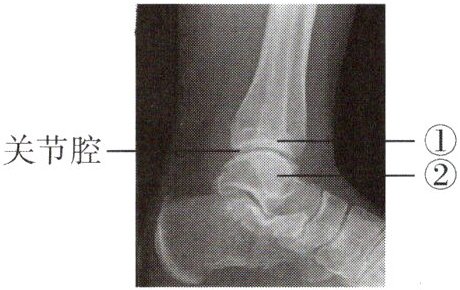

3. 下图为某人的踝关节射线透视图像,①②表示踝关节的组成结构。下列说法错误的是(

A.①是关节头,②是关节窝

B.①②表面覆盖着关节软骨

C.关节腔内有滑液,使关节灵活

D.踝关节在运动中起支点作用

A

答案:

A 解析:题图中的①是关节窝,②是关节头;①关节窝、②关节头表面覆盖着关节软骨;关节腔内有滑液,能减少骨与骨之间的摩擦,使关节灵活;运动中,神经系统起调节作用,骨起杠杆作用,关节起支点作用,故踝关节在运动中起支点作用。